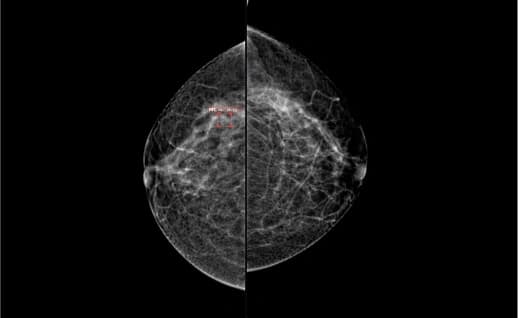

L CC R CC

L MLOR MLO

An AI-powered solution efficiently detects pathologies in medical imaging, including cancer, cancer nodules in the early stages. It supports X-rays, CT scans, and MRIs, reducing diagnosis time and enhancing hospital capacity by streamlining workflows.